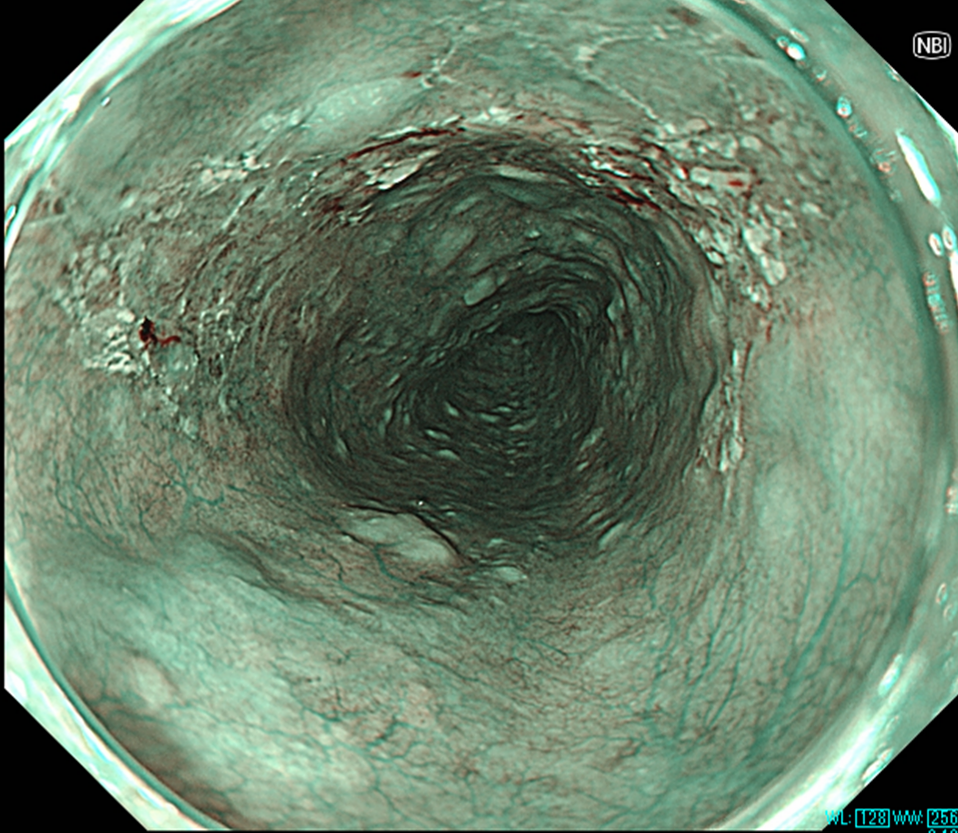

食道表在癌のNBI画像(左)およびNBI+TXI画像(右)の比較

NBI+TXIでは明度の上昇や輪郭の強調により腫瘍の存在が強調される。